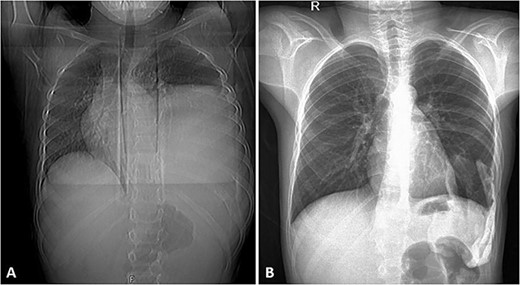

(A) Frontal chest radiograph of the same patient showing a left-sided opacity involving the left middle and lower lung zones and silhouetting the diaphragm and the left cardiac border in keeping with the known huge left posterior chest wall tumor. Widening of the posterior aspect of the left 10th intercostal space is noted. (B) Frontal chest radiograph taken during follow-up visits ~2 years following the surgical resection of the tumor, it shows re-expansion of the left lung with no residual or recurrent masses.